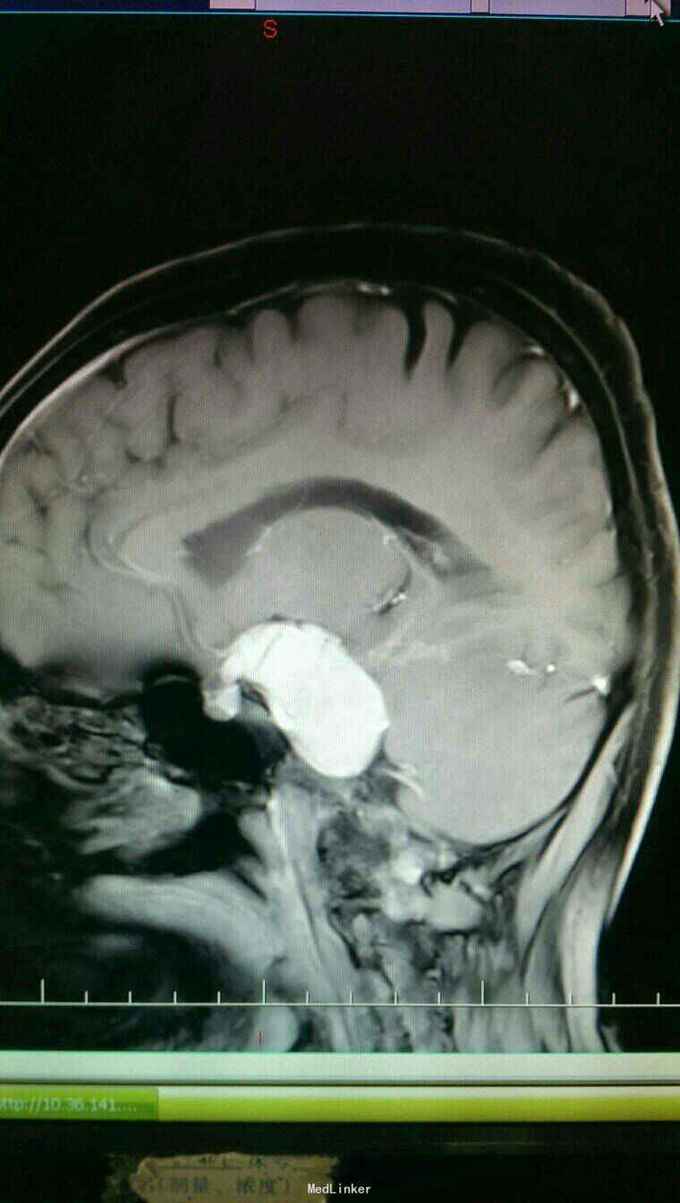

患者以头晕伴走路不稳一个月为主诉入院。患者于入院一个月前自觉头晕,无头痛,无恶心,呕吐。走路不稳,无四肢抽搐及二便失禁。

查体:神志清楚,语言流利。双侧瞳孔等大正圆,直径3.0毫米,光反射灵敏。饮水呛咳,无声音嘶哑。颈软,四肢肌力正常,生理反射存在,病理反射未引出。

入院诊断:岩斜区脑膜瘤。完善术前准备,于全麻下行右侧颞下入路,岩斜区肿瘤切除,术中保留拉贝静脉,剪开小脑幕,近全切除肿瘤。

患者术后病情稳定,岩斜区位于颞骨岩部背面与枕骨斜坡部的岩斜裂汇合处,从岩骨尖至颈静脉孔。内侧至斜坡中线,外侧至第Ⅴ、Ⅶ和Ⅷ脑神经,上缘为鞍背,下缘为颈静脉孔水平;下方为枕骨大孔区。岩斜区脑膜瘤由于位置深,毗邻重要解剖结构,很难实现肿瘤全切除,且有较高的术后致残率,一直是神经外科手术的治疗难点。颅内脑膜瘤约0.3%~1.0%起源于岩斜区,是岩斜区最常见病变。它向上可侵犯岩骨尖、小脑幕、Meckel腔、鞍旁和海绵窦;向下侵犯内听道和颈静脉孔;向内侧达脑干和椎-基底动脉。当肿瘤很大时,可包绕同侧Ⅲ~Ⅺ脑神经。患者临床可表现头痛、复杂的脑神经麻痹、共济失调等症状,严重者表现为偏瘫、认知功能障碍。岩斜区脑膜瘤多数表现良性过程,目前,仍以手术切除为首选治疗方式。 岩斜区脑膜瘤手术技术非常关键,需要熟悉岩斜区解剖关系并有丰富的显微操作经验。在术前放置腰穿引流,或术中甘露醇应用可明显降低脑组织压力,减少牵拉造成的副损伤。提前对脑膜瘤基底的处理可有效避免肿瘤持续出血造成的蛛网膜界面消失。肿瘤的生长将神经、血管拉伸或包绕,尤其是复发的肿瘤,会破坏蛛网膜界面,侵犯脑干软脑膜。手术时应仔细分辨和保护。肿瘤囊壁与神经、血管外膜和脑干粘连,不应勉强分离,以保护下方结构。 待术后平稳复查头Ct。